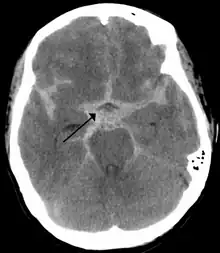

The following are images from various Medicine-related articles on Wikipedia.